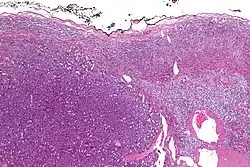

| Micrograph of an adrenocortical carcinoma (left of image – dark blue) and the adrenal cortex it arose from (right-top of image – pink/light blue). Benign adrenal medulla is present (right-middle of image – gray/blue). H&E stain. | |